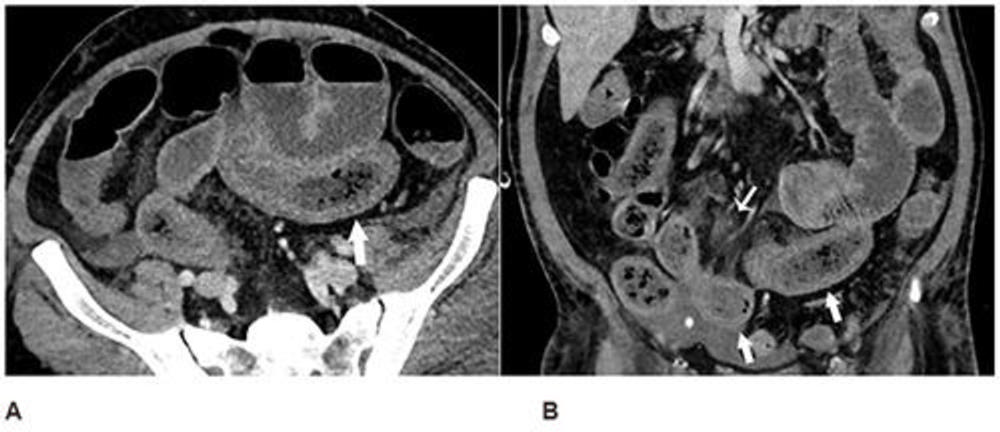

Figure 1. Axial (A) and coronal (B) CT of the abdomen and pelvis with IV contrast in a 57-year-old man with a high clinical suspicion for bowel ischemia. There was generalized small bowel distension and segmental thickening (arrows), with adjacent mesenteric congestion (thin arrow in B), and a small volume of ascites (* in B). Findings are nonspecific but suggestive of early ischemia or infection.